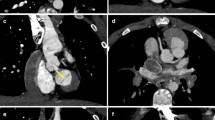

Kawasaki disease is a febrile systemic vasculitis of unknown origin that usually occurs in infancy and childhood. The acute phase is characterized by high fever, cutaneous rash, non-exudative conjunctivitis, oral mucosa inflammation, cervical adenopathy, swollen hands and feet, red palms and soles, and subungual peeling [58]. Acute cardiac manifestations include pericarditis, myocarditis, heart valve dysfunction and arrhythmias. About 15–25% of patients, especially when not treated early with high-dose intravenous immunoglobulins, develop coronary artery aneurysms, which sometimes undergo thrombosis and progressive stenosis causing myocardial ischemia, infarction and sudden death [59]. Coronary aneurysms are more commonly located along the proximal left and right coronary arteries, but any segment can be affected. They can be saccular or fusiform, or there can be diffuse ectasia without segmental dilation. They can evolve over time in shape and size, increasing in dimension over the first 1–2 months after the onset of the disease and regressing in up to two-thirds of cases to normal lumen diameter within 2–5 years [60], with further regression being unlikely. Therefore, imaging follow-up of the coronary arteries is essential in these children. Echocardiography has high diagnostic accuracy for proximal aneurysms, but it is less sensitive for distal lesions and coronary artery stenosis, which usually worsens over time in the affected segments. For these reasons, CT is widely used to obtain high-resolution imaging of the whole coronary tree [4, 61] (Figs. 10 and 11), offering comparable accuracy to conventional angiography [62]. In case of giant aneurysms, repeating the scan at equilibrium contrast-phase might help to differentiate thrombosis from flow artifacts and depict persistent myocardial perfusion defects (Fig. 12).

Kawasaki disease and giant aneurysms in a 2-year-old girl. a First-pass horizontal long-axis reformatted CT image documents a giant aneurysm of the middle right coronary artery with no visible lumen (circle) but cannot differentiate between thrombus and flow artifact. b Similar horizontal long-axis reconstruction at equilibrium contrast-phase confirms the finding, distinguishing between patent lumen (arrowhead) and eccentric thrombus (arrow). c, d Vertical long-axis (c) and mid-ventricular short-axis (d) views at equilibrium contrast-phase also demonstrate a persistent subendocardial perfusion defect of the left ventricular mid-basal inferior wall from ischemia/infarct (arrows)